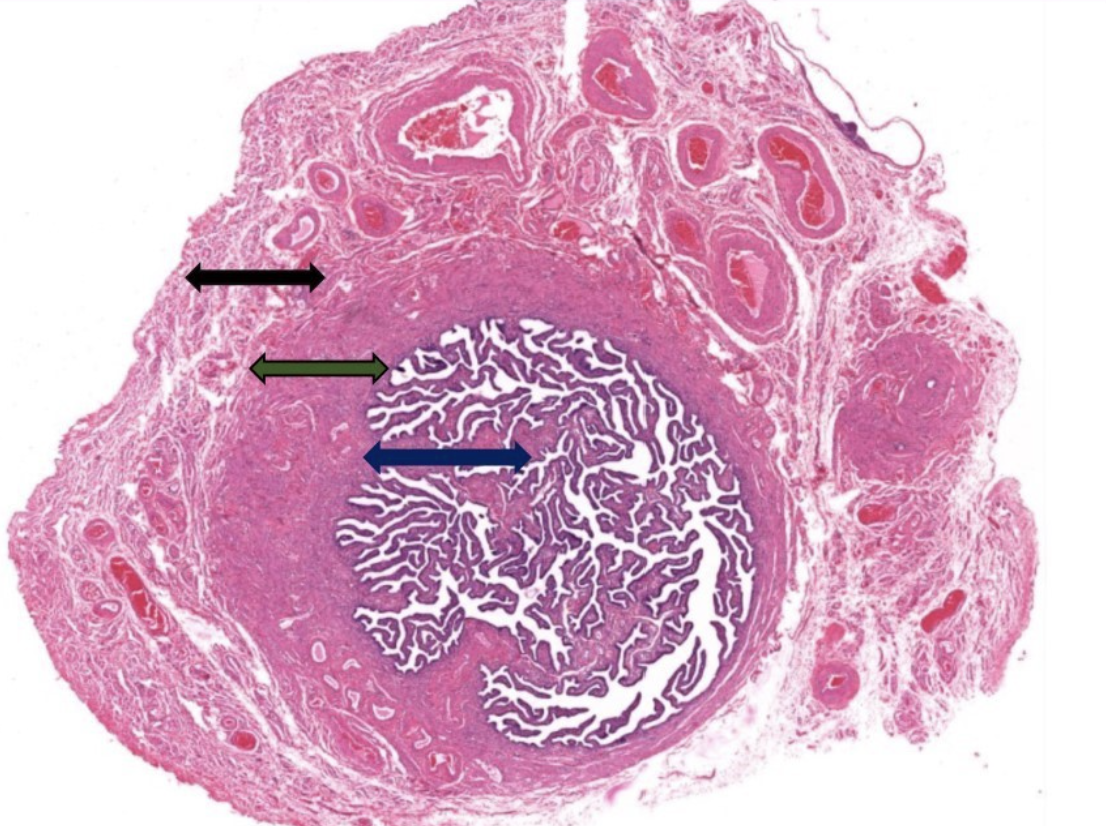

label this slide

ampulla of oviduct